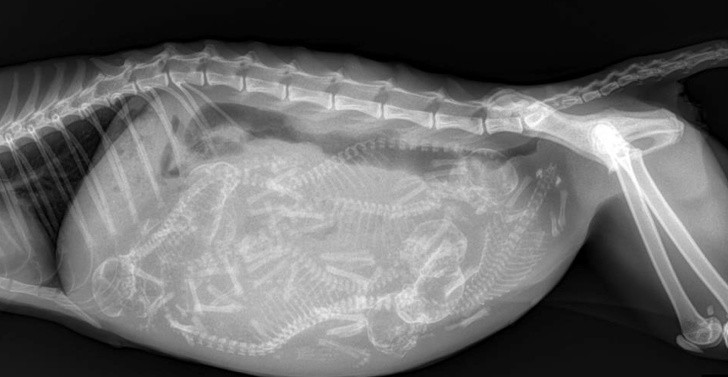

Gli esseri umani sono creature davvero strane e possono accaderci cose incredibilmente bizzarre. Queste radiografie sconvolgeranno anche coloro che pensano di aver visto tutto.

Raggi X È una delle migliori invenzioni dell'umanità e in alcune situazioni è indispensabile. Soprattutto perché spesso accade che le persone, soprattutto i bambini, deglutire cibi che non fanno parte della dieta quotidiana. Per non parlare dei cani che cercano di masticare tutto ciò che vedono e, quindi, spesso ingoiano cose inappropriate.

I radiologi sono già abbastanza abituati a vedere i raggi X cose strane e alcune di quelle che abbiamo raccolto per voi nella galleria non li hanno affatto sorpresi. Ecco qui 15+ radiografie stravaganti e a volte scioccanti.